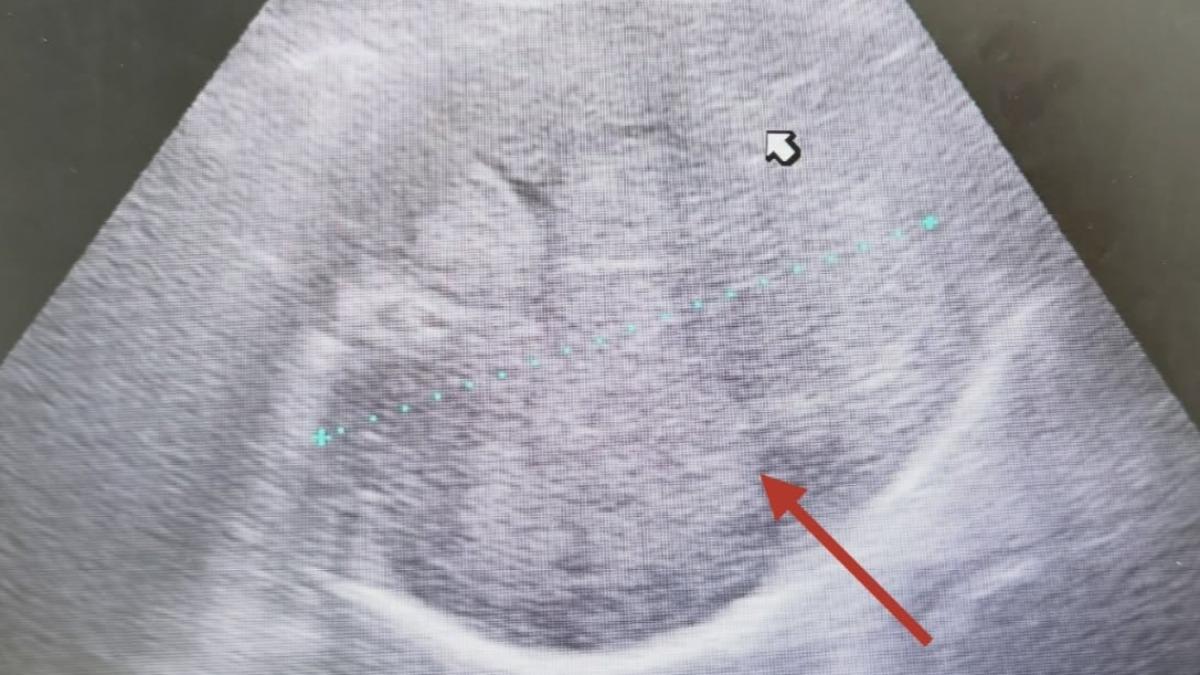

台中市一名64歲的蔡姓男子,平時生活單純,沒有抽菸、不良嗜好,但因為有肺癌家族史,近日仍照往例前往豐原醫院健檢,結果經胸腔外科醫師蕭凱宇檢查,蔡男雙側肺部有10多顆大小不一的肺部結節,評估確診肺腺癌,對此,蕭凱宇也提醒,肺癌早期沒有明顯症狀,,由於肺部缺乏痛覺神經,往往出現血痰、胸痛、胸悶、喘、骨痛、頭痛時,已經是中晚期,五年存活率也將大幅下降。